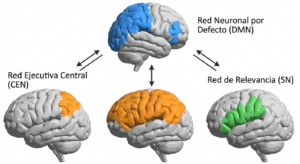

Mediante el rs-fMRI y el análisis de grafos, enfocados a la neurociencia, se han encontrado muchas redes intrínsecas. Pero, tres resaltan por su importancia en la organización mental y su impacto en la patología:

1. La Red Neuronal por Defecto (Default Mode Network – DMN)

Raichle la descubrió casi sin querer en 2001, y la DMN, podría decirse, que es el hallazgo más renombrado de la neurociencia actual.

Esta red, que abarca centros neurálgicos, por ejemplo, la corteza cingulada posterior (PCC), el precúneo, y la corteza prefrontal medial (mPFC), se enciende a full cuando no estamos prestando atención al mundo exterior.

La DMN, esta es el base neurológica de la cognición dirigida al interior como soñar despierto, la memoria autobiográfica, la reflexión en el porvenir y la teoría de la mente que trata sobre pensar en lo que otros piensan. Es muy crucial para consolidar la identidad propia, lo sabias? Su hiperactividad se relaciona con la rumiación en la depresión, al tiempo que su hipoactividad o un desarrollo alterado, se puede ver en el trastorno del espectro autista.

2. La Red Ejecutiva Central (CEN).

Esta Red Ejecutiva Central, funciona de manera antagonista a la DMN, con sede en la corteza prefrontal dorsolateral (dlPFC) y la corteza parietal posterior lateral. Esta red se «activa» cuando necesitamos utilizar recursos cognitivos para tareas externas: memoria de trabajo, solución de problemas complicados, inhibir respuestas y atención sostenida.

En cerebros sanos, la DMN y la CEN mantienen una relación «anticorrelacionada»; cuando una se activa, la otra, se tiene que suprimir.

La inabilidade de apagar la DMN cuando hay tareas que piden atención de afuera es como la huella dactilar en desordenes cognitivos y atencionales variados.

3 La Red de Relevancia (Salience Network SN).

Si la DMN trabaja pal mundo interno, y la CEN pal externo, ¿Quién decide a que hay que ponerle ojo? Ese es el curro de la Red de Relevancia. Ubicada en la ínsula anterior y la corteza cingulada anterior dorsal (dACC), la SN actúa como un «interruptor» activo.

La SN checa, constantemento, el fluir de la información sensorial e interoceptiva (desde el cuerpo) con el fin de pillar eventos biológicamente importantes (dolor, una cara que da miedo, un error del coco). Si nota algo importante, la SN manda señales para que se apague la DMN y la CEN se ponga a laburar en la situación. El mal funcionamiento de la ínsula anterior, pieza central de la SN, se le ha achacado a la esquizofrenia (en donde lo que viene de adentro y no importa se cree superimportante, ej. alucinaciones) y en los transtornos de ansiedad.

El diseño de las Redes Funcionales Intrínsecas. Este mapa revela la posición de las tres «super-redes» cognitivas en la corteza. Arriba (Azul): Red por Defecto (DMN), funcionando en la cognición interna. Centro (Naranja): Red Ejecutiva Central (CEN), que está activa cuando hay tareas externas. Abajo (Verde): La Red de Relevancia (SN), que funge como un cambio dinámico entre la DMN y la CEN, hallando estímulos cruciales.